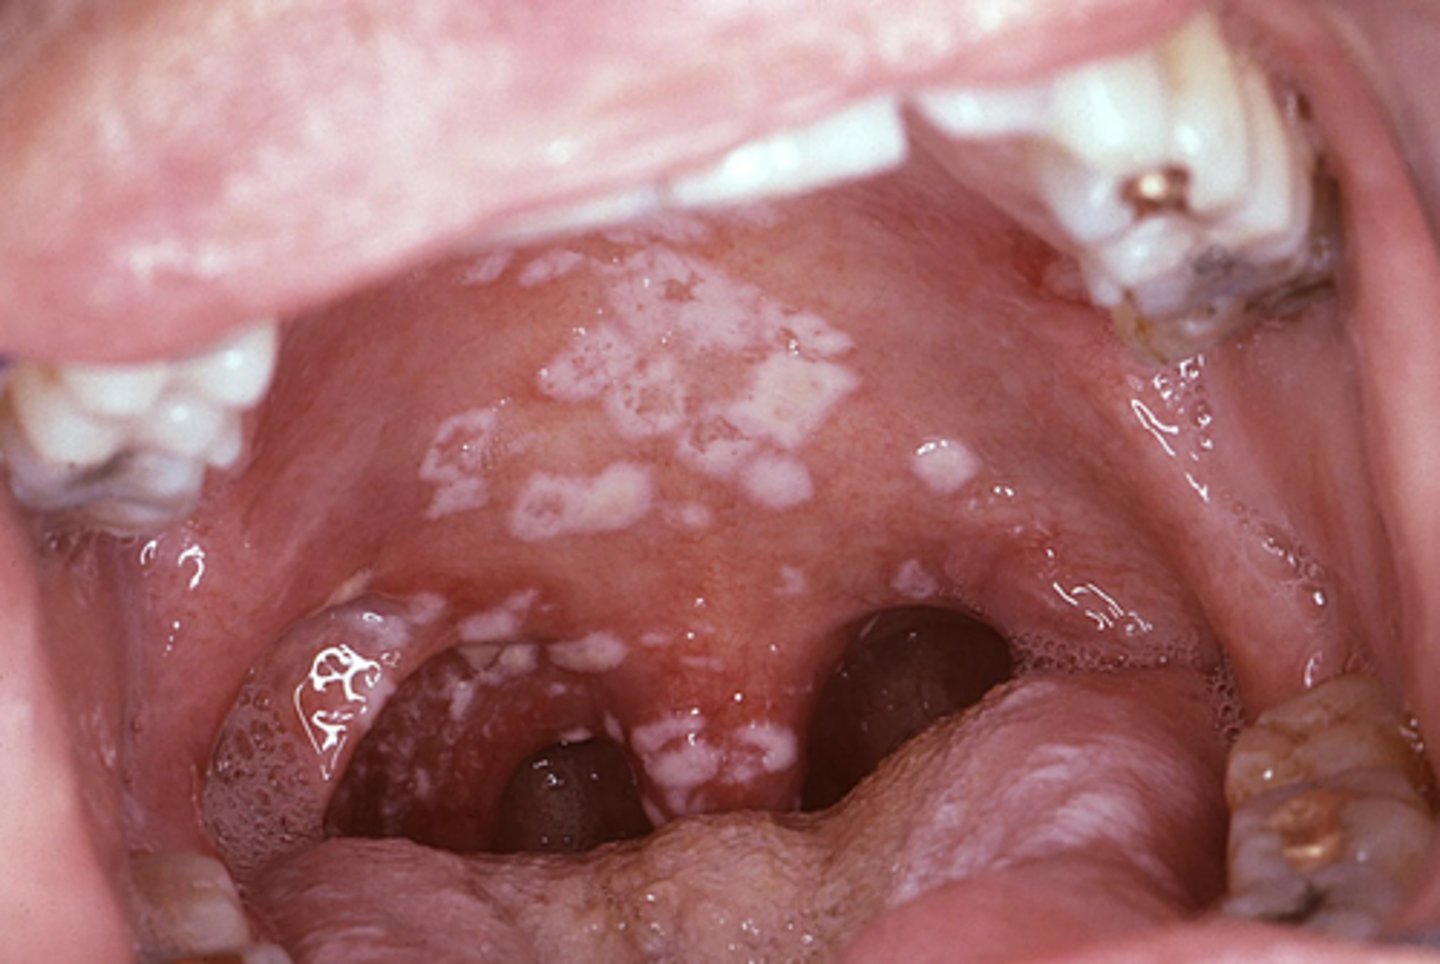

Multiple grayish-white mucosal patches ar present throughout the oral cavity.

secondary syphillis